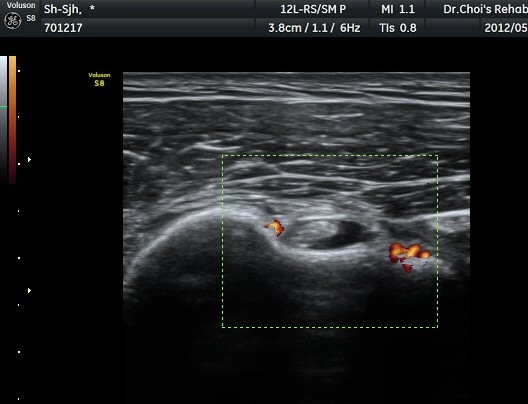

°Ë»ç¿¡¼­ Ç÷·ùÁõ°¡°¡ °üÂûµÈ´Ù(»çÁø 2). À̵ιڱ٠Á¾´Ü¸é°Ë»ç¿¡¼­µµ °Ç ÁÖÀ§ ¼ö¾×Àú·ù°¡ È®ÀÎ

µÈ´Ù(»çÁø 3). ±Ø»ó°Ç Á¾´Ü¸é°Ë»ç»ó ±Ø»ó°Ç ºÎÂøºÎ¿¡ °í¿¡ÄÚ µ¢¾î¸®°¡ °üÂûµÇ°í(»çÁø 4, 5)